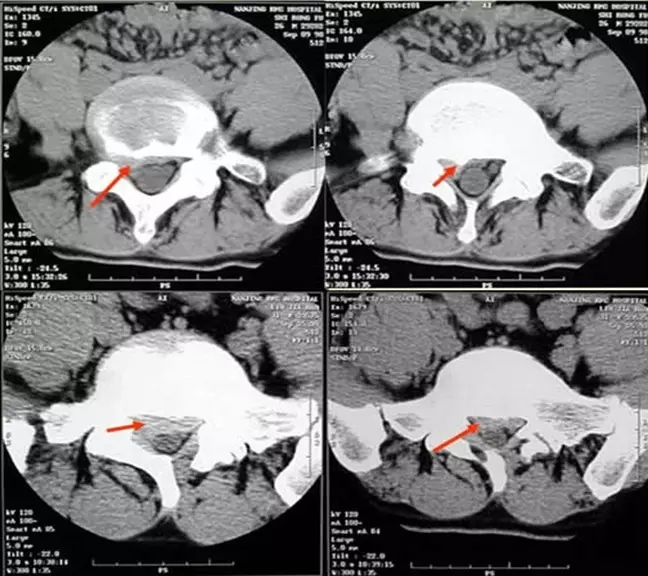

4.滑脱、峡部裂

腰椎前滑脱I度

椎弓峡部裂